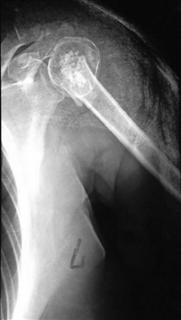

Лечение внутрисуставных переломов плечевой кости и костей предплечья представляет непростую задачу. Травмы верхней трети плечевой кости происходят в результате падения на вытянутую руку, вывихов и переломовывихов в плечевом суставе. Такие переломы обычно включают раскалывание головки плеча на несколько фрагментов и смещение костных отломков в области хирургической шейки плечевой кости.

Рис.1. Пациентка, 58 лет. Закрытый перелом хирургической шейки левой плечевой кости со смещением костных отломков.